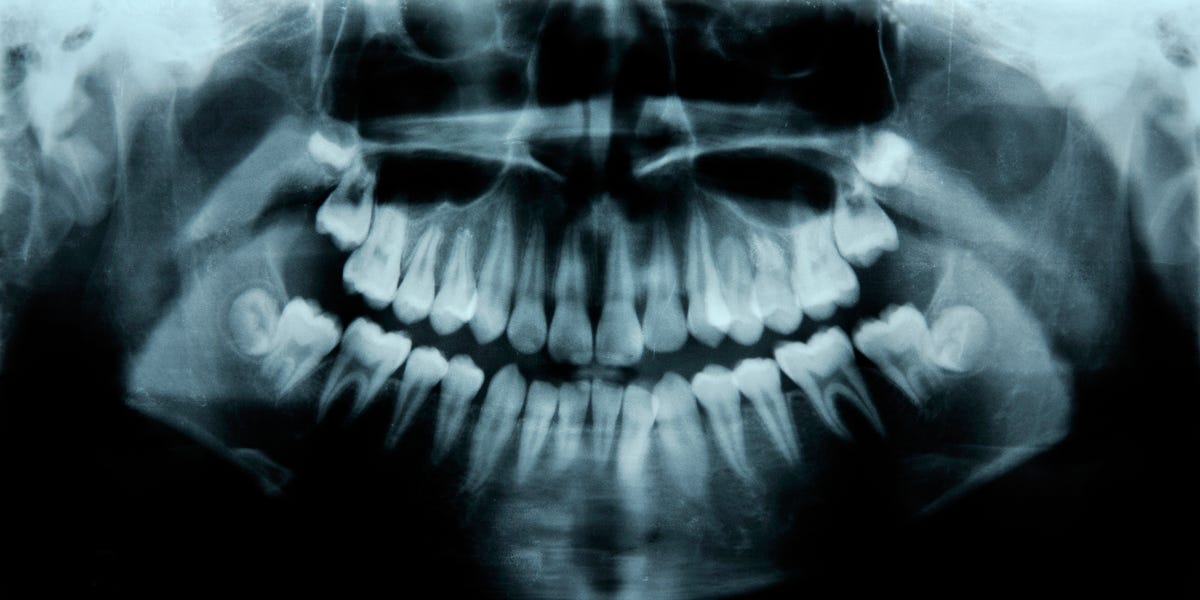

cm0002@infosec.pub to Science@mander.xyz · 6 days agoHumans Have a Third Set of Teeth. New Medicine May Help Them Grow.www.popularmechanics.comexternal-linkmessage-square17fedilinkarrow-up159